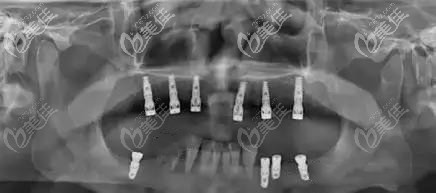

上頜即拔即種后的CT片▼

上半口即刻種植后戴的臨時牙冠▼